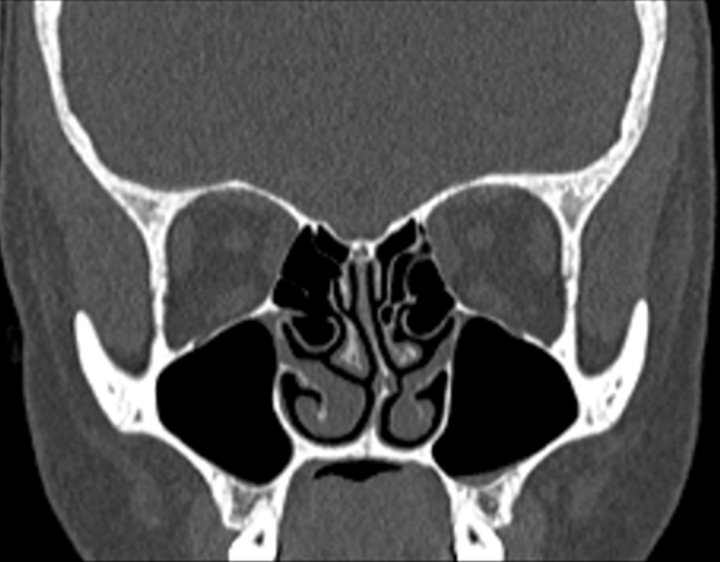

001